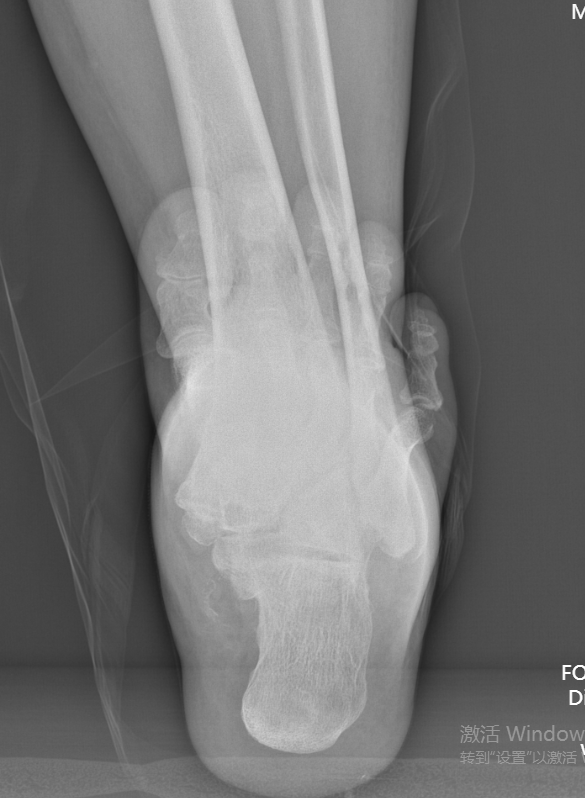

第一台手术的患者是位75岁的叔叔,被“脚脖子”痛缠了4年,疼得越来越厉害,病情已经到了严重阶段。

术前后足力线X线

武勇主任团队给他做了3D打印导板辅助下人工全踝关节置换术。

这种手术适合踝关节病严重的患者,通过替换病变的关节结构,能帮着缓解疼痛、恢复关节活动,让老人日常走路更自在些。